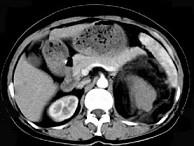

问题 女,64岁,左侧腰部胀痛,行CT扫描,下列说法正确的是 ( )

选项 A、考虑为左侧肾上腺来源的髓样脂肪瘤 B、考虑为腹膜后来源的脂肪肉瘤 C、该病灶密度不均匀,其内可见脂肪密度影,且呈不均匀强化 D、考虑为左肾来源的血管平滑肌脂肪瘤 E、左肾区可见一巨大的占位性病灶,境界较清楚,胰腺尾部受压向前推移

答案 CDE